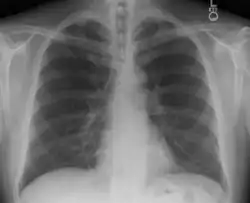

Рентгеногра́фия органов грудной клетки — классическое проекционное рентгенографическое исследование грудной клетки, применяемое для диагностики патологических изменений грудной клетки, органов грудной полости и близлежащих анатомических структур. Рентгенография грудной клетки является одним из наиболее распространённых рентгенографических исследований.

При изучении рентгеноанатомии органов грудной клетки обращают внимание на рентгеновскую структуру видимых костей и мягких тканей грудной клетки; форму и прозрачность для рентгеновских лучей областей, на которые проецируется лёгочная ткань (так называемых «лёгочных полей»), а также их структуру, сформированную тенями сосудов лёгких («лёгочный рисунок»); расположение и структурность корней лёгких; положение, форму куполов диафрагмы и синусов плевральных полостей; форму и размеры тени средостения (в том числе сердца).

Рентгенография грудной клетки способствует выявлению патологических изменений мягких тканей, костей грудной клетки и анатомических структур, расположенных в грудной полости (лёгких, плевры, средостения). Наиболее часто при рентгенографии диагностируются пневмония и застойная сердечная недостаточность. Наряду с диагностическими целями, рентгенография грудной клетки используется в качестве скринингового метода для оценки состояния лёгочной ткани, в частности, у лиц с профессиональными вредностями (например, шахтёров)[2].

Дополнительные или отсутствующие теневые элементы (затемнения и просветления, снижение или повышение прозрачности лёгочного фона, обогащение или обеднение лёгочного рисунка и т. д.) в теневой картине лёгочной ткани свидетельствуют о патологии. Каждый из дополнительных теневых элементов обладает определёнными характеристиками (положение, число, форма, размеры, интенсивность, структура, контуры, смещаемость), не только имеющими клиническое значение, но и способствующими дифференциальной диагностике, а также имеющими практическую ценность при планировании бронхоскопии, биопсии, оперативного вмешательства и т. д.

В числе патологических рентгенологических находок выделяют очаги или фокусы (ограниченные участки затемнения лёгочной ткани), воздушные полости (участки просветления на фоне лёгочной ткани), плевральный выпот (затемнение плевральных синусов и междолевых щелей или пристеночное затемнение различной распространённости), воздух в плевральной полости (прослеживается тонкая линия висцеральной плевры, отделённая от грудной клетки участком просветления, лишённым лёгочного рисунка), различные типы диффузных изменений (ретикулярный, милиарный, кистозный, по типу «матового стекла», зоны диффузной консолидации).